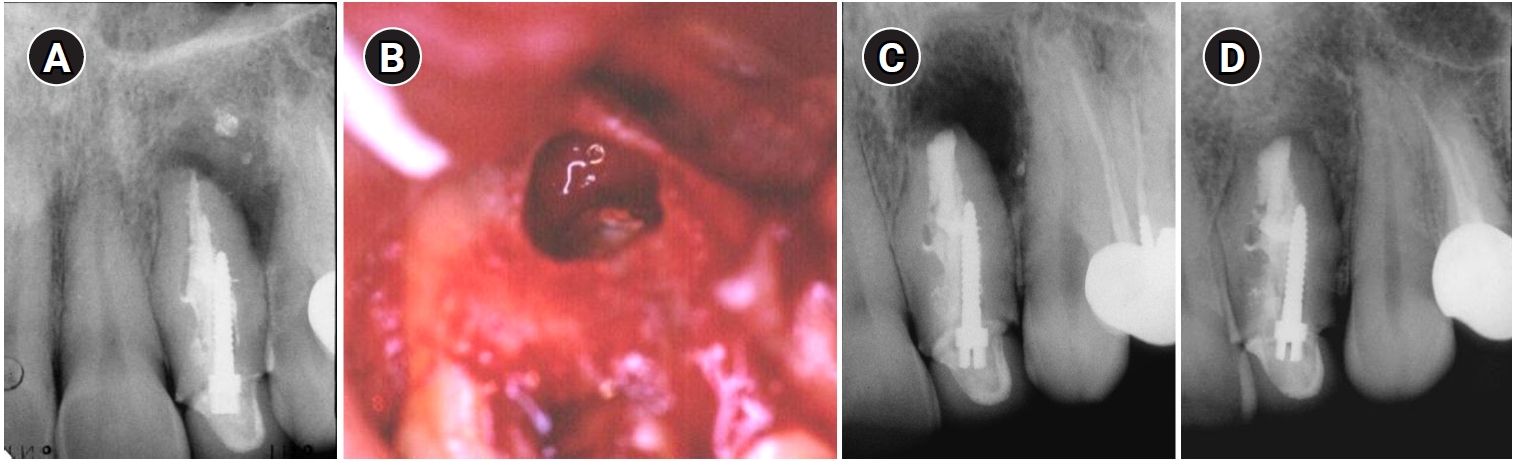

Thirty years later (2002), the patient came back to the department with a complaint of pain and swelling and was diagnosed with an acute apical abscess in tooth #22. Informed consent was obtained and endodontic surgery was performed in the department (Figure 2). The tooth was treated with a modern surgical endodontic protocol, involving a dental operating microscope: local anesthesia with lidocaine 2% with epinephrine 1:100,000, triangular full mucoperiosteal flap, osteotomy, root-end resection with no bevel using a high-speed bur, curettage, retrograde preparation using ultrasonic tips, and root-end filling with intermediate restorative material (IRM; L.D. Caulk Company, Milford, DE, USA).

Clinical and radiographic follow-up was scheduled annually. Radiographic outcomes were assessed based on the criteria established by Rud et al. [17]. At a 2-year follow-up, the tooth was clinically asymptomatic, with good adaptation of the crown to the tooth and with radiographically normal periapical tissue (Figure 2C). The tooth remained asymptomatic with radiographically complete healing at an additional follow-up visit in 2006 (Figure 2D).